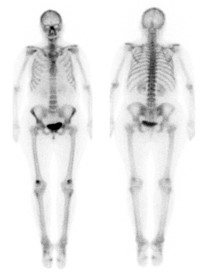

Nuclear medicine bone scan

Nuclear medicine is a subspecialty within radiology. It comprises diagnostic examinations that result in images of body anatomy and function. The images are developed based on the detection of energy emitted from a radioactive substance given to the patient, either intravenously or by mouth. Generally, radiation to the patient is similar to that resulting from standard X-ray examinations.